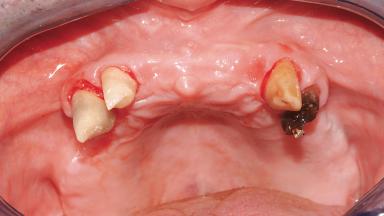

Immediate Loading of Six Implants in the Maxilla and Final Restoration with a Full-Arch Gold/Ceramic FDP Involving the Concept of Tilted Implants

A 61-year-old male patient with a failing fixed maxillary rehabilitation and a fixed mandibular rehabilitation requested a new fixed maxillary rehabilitation. The patient was wearing a temporary metal-reinforced maxillary bridge inserted two years before the consultation. He reported that his previous dentist did not want to insert a definitive framework because he considered the residual teeth to have a negative prognosis. The patient reported a history of recurrent caries and endodontic complications as the main reason for the previous extractions. The anamnesis was negative for periodontal disease and bruxism. The patient’s chief compliant was the mobility of his maxillary prosthesis, which needed to be re-cemented frequently, and discomfort during chewing.Moreover, the patient was not satisfied with the esthetic appearance of his maxillary teeth, which he found too long. The patient asked for a stable and comfortable fixed maxillary rehabilitation and firmly rejected any removable solution.